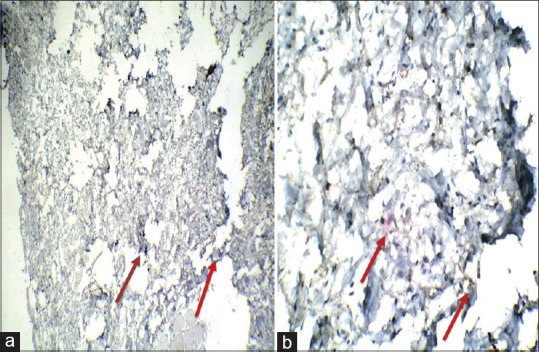

Materials and methods: The study group was divided into the four groups of 25 patients in each group. Group A were patients having healthy periodontium and without any systemic diseases. Group B were patients having periodontitis without any systemic diseases. Group C were patients having both periodontitis and DM. Group D were patients having only DM without any periodontitis. The VEGF levels were graded into three grades of 0, 1 and 2. They were evaluated through immunohistochemistry in tissue samples obtained from all the groups.

Results: Healthy patients generally had Grade 0 level whereas patients having only periodontitis or only DM had primarily Grade 1. Most of the patients having both periodontitis and diabetes had Grade 2 level of VEGF.